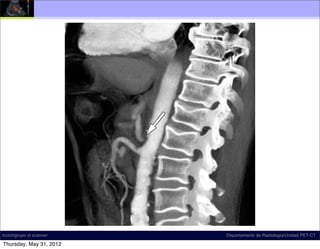

Diagnóstico: ????

T12-L1

incich/grupo ct scanner              Departamento de Radiología/Unidad PET-CT